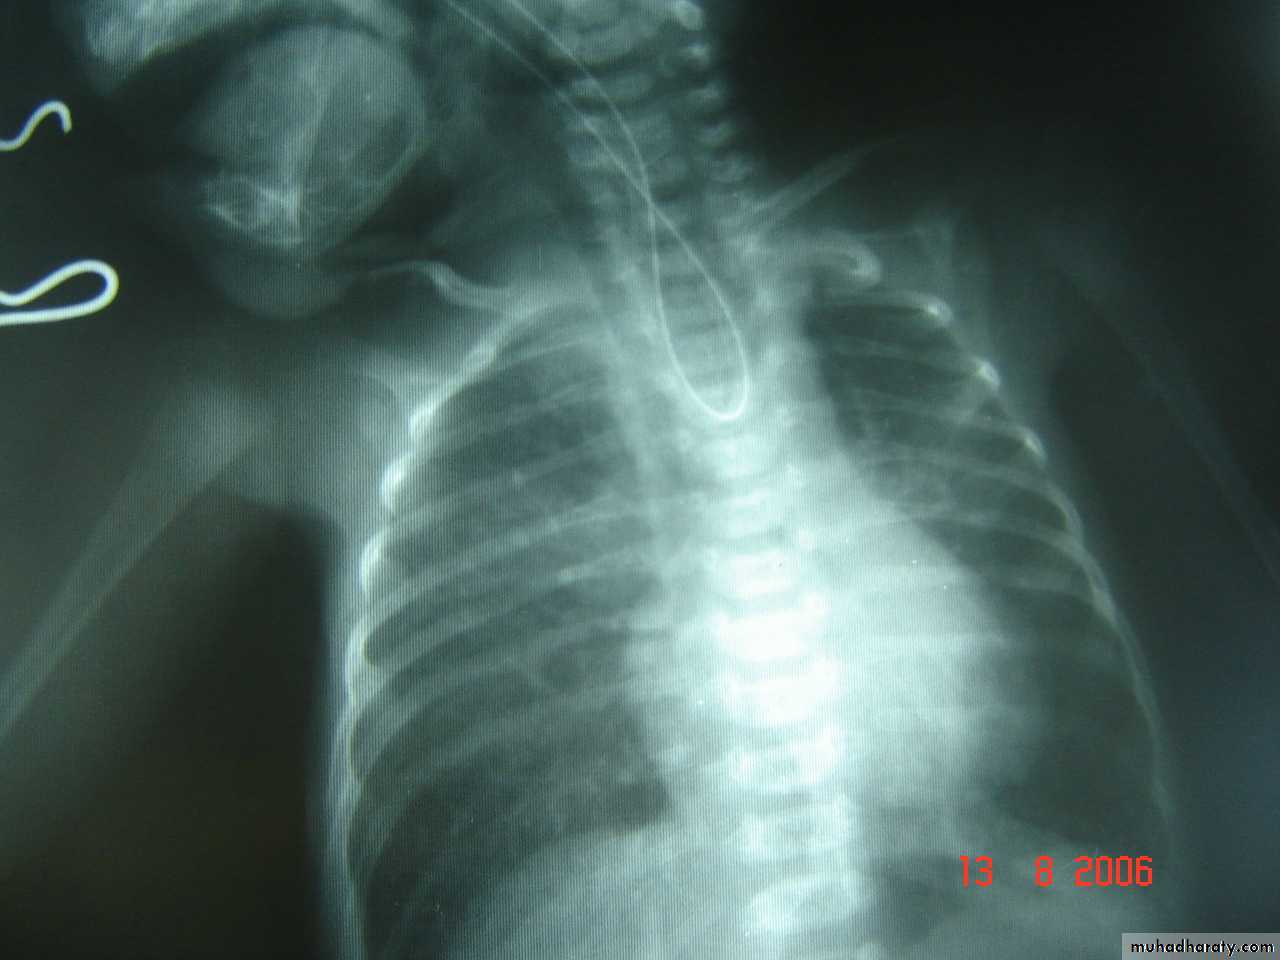

What is the diagnosis?

What are the Diffrential diagnosis?Timing of operation?

What is the diagnsis?